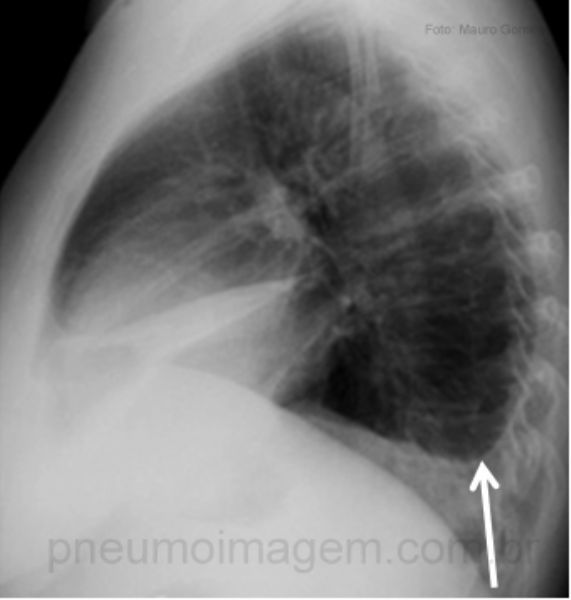

Sinal de Lemos-Torres - abaulamento do espaço intercostal quando da expiração

Linha de Damoiseau

(Decúbito lateral com raios horizontais)